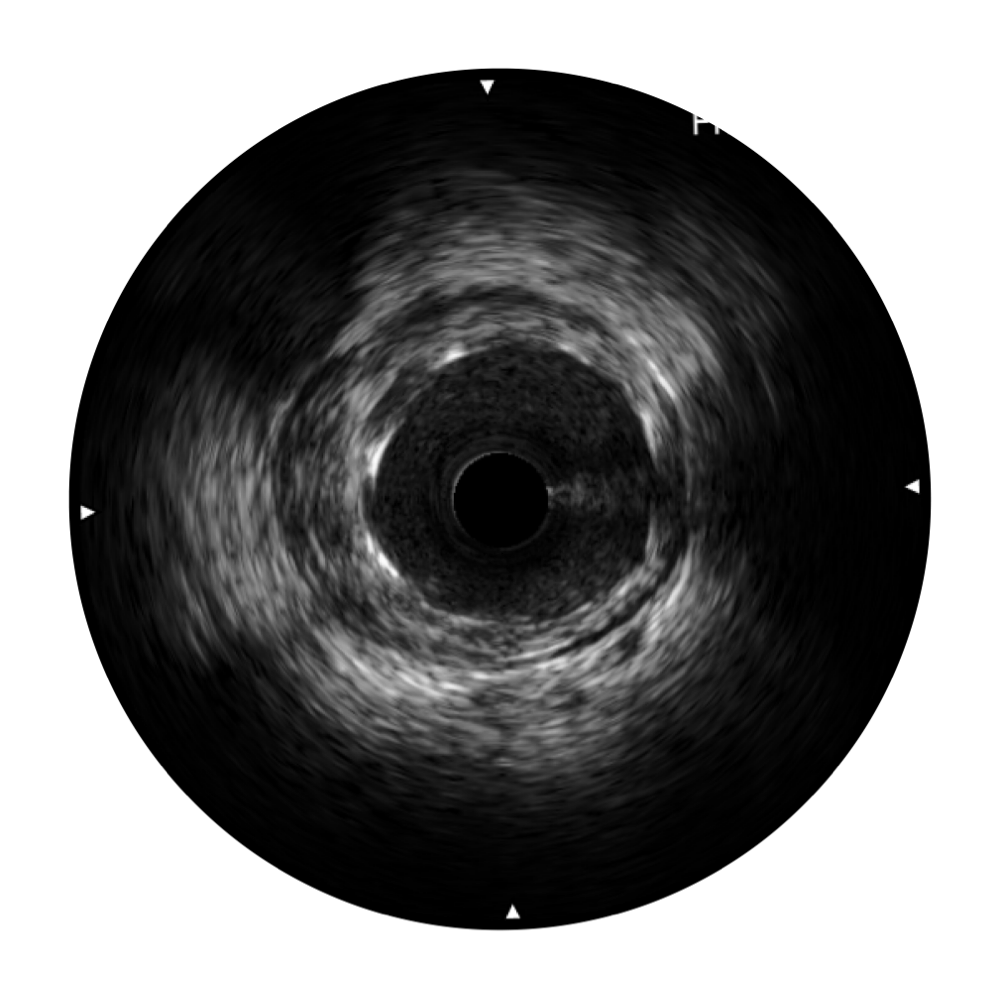

开立宽频IVUS图像

对比传统IVUS导管成像,开立宽频IVUS图像的近场支架梁显影更细腻,远场中膜外血管仍清晰可辨,兼顾远中近,兼顾分辨力与穿透深度